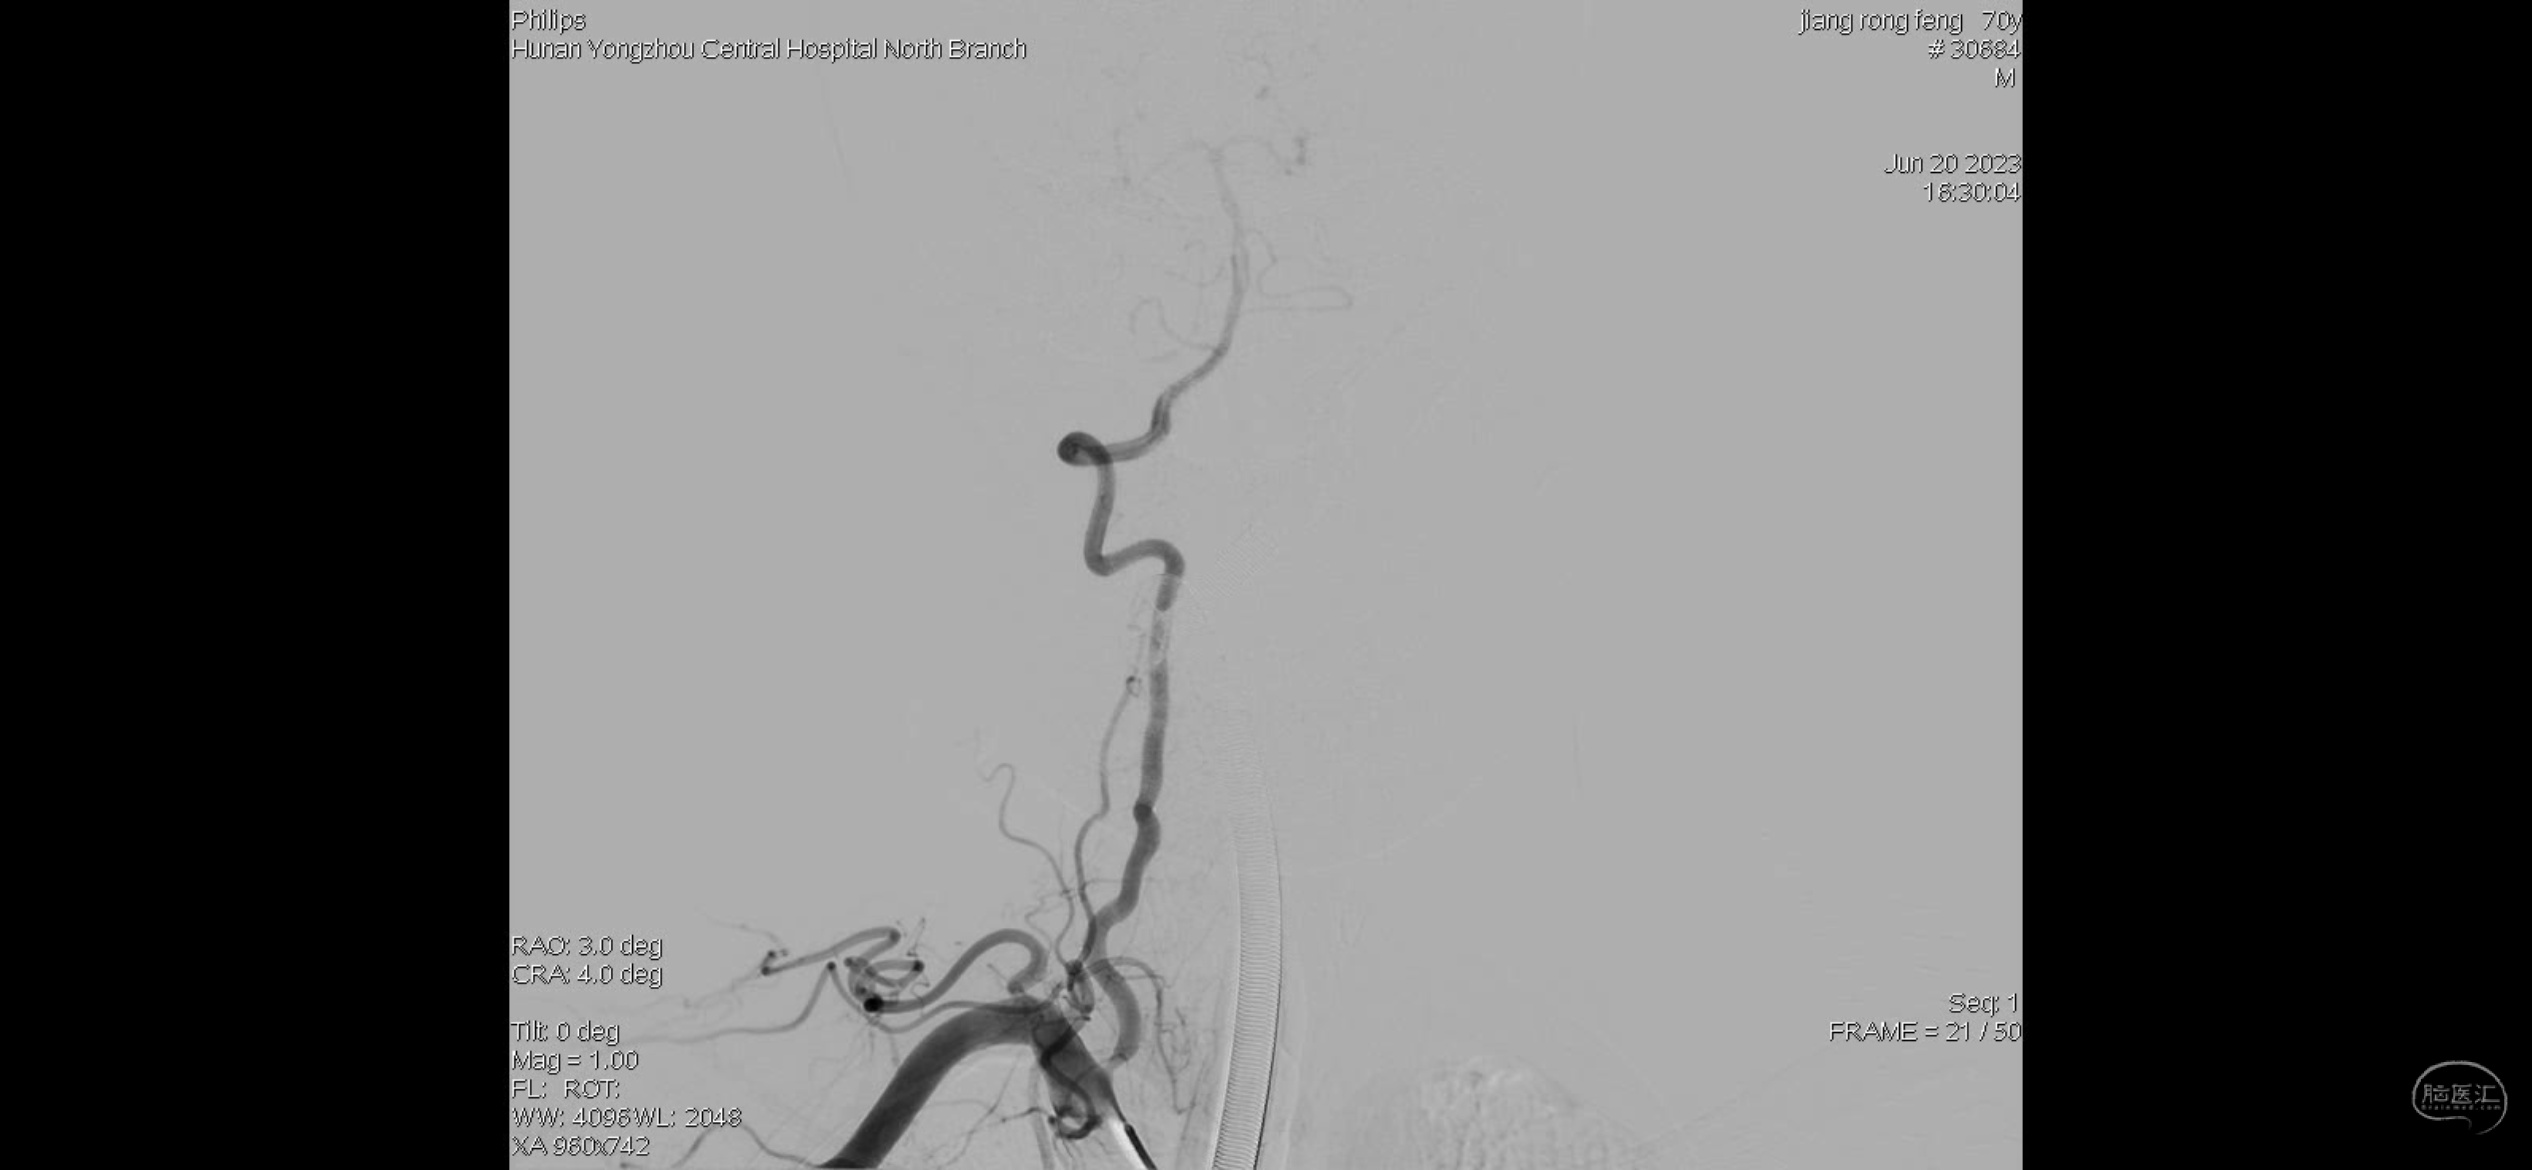

右侧椎动脉V1段狭窄,准备药物治疗随访。

左侧颈内动脉C1段狭窄血流无影响,无向右侧代偿血流,治疗上也是药物治疗后随访。

右侧考虑颈内动脉C1段重度狭窄合并急性闭塞,眼动脉反流显影部分血管,右侧M1分叉部急性闭塞,右侧大脑前血流考虑血流灌注不足影响,且合并A2狭窄。